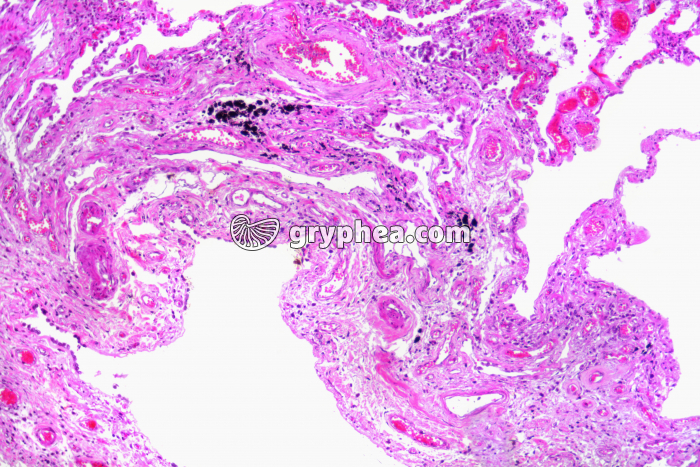

Poumon fumeur x25

Les poumons sont des organes permettant, en milieu aérien, les échanges de gaz respiratoires (dioxygène et dioxyde de carbone) entre l’organisme et le milieu ambiant. Ils sont dotés d’une grande quantité de petits sacs pulmonaires minuscules, constitués d’alvéoles aux parois extrêmement minces, qui facilitent les échanges de gaz entre l’air alvéolaire et le sang des capillaires qui tapissent les alvéoles. Au microscope, les poumons se caractérisent par une structure lacunaire, l’essentiel du tissu pulmonaire étant occupé par des cavités optiquement vides, les alvéoles. Il est possible, sur les coupes à plus faible grossissement, d’identifier des bronchioles en coupe, ainsi que des vaisseaux sanguins (artérioles et veinules).

Les pathologies des poumons sont très diverses et complexes. Elles peuvent être dues au tabagisme, à une maladie microbienne ou génétique, au séjour prolongé dans des milieux où les aérosols, solides ou gazeux, sont abondants,[...]